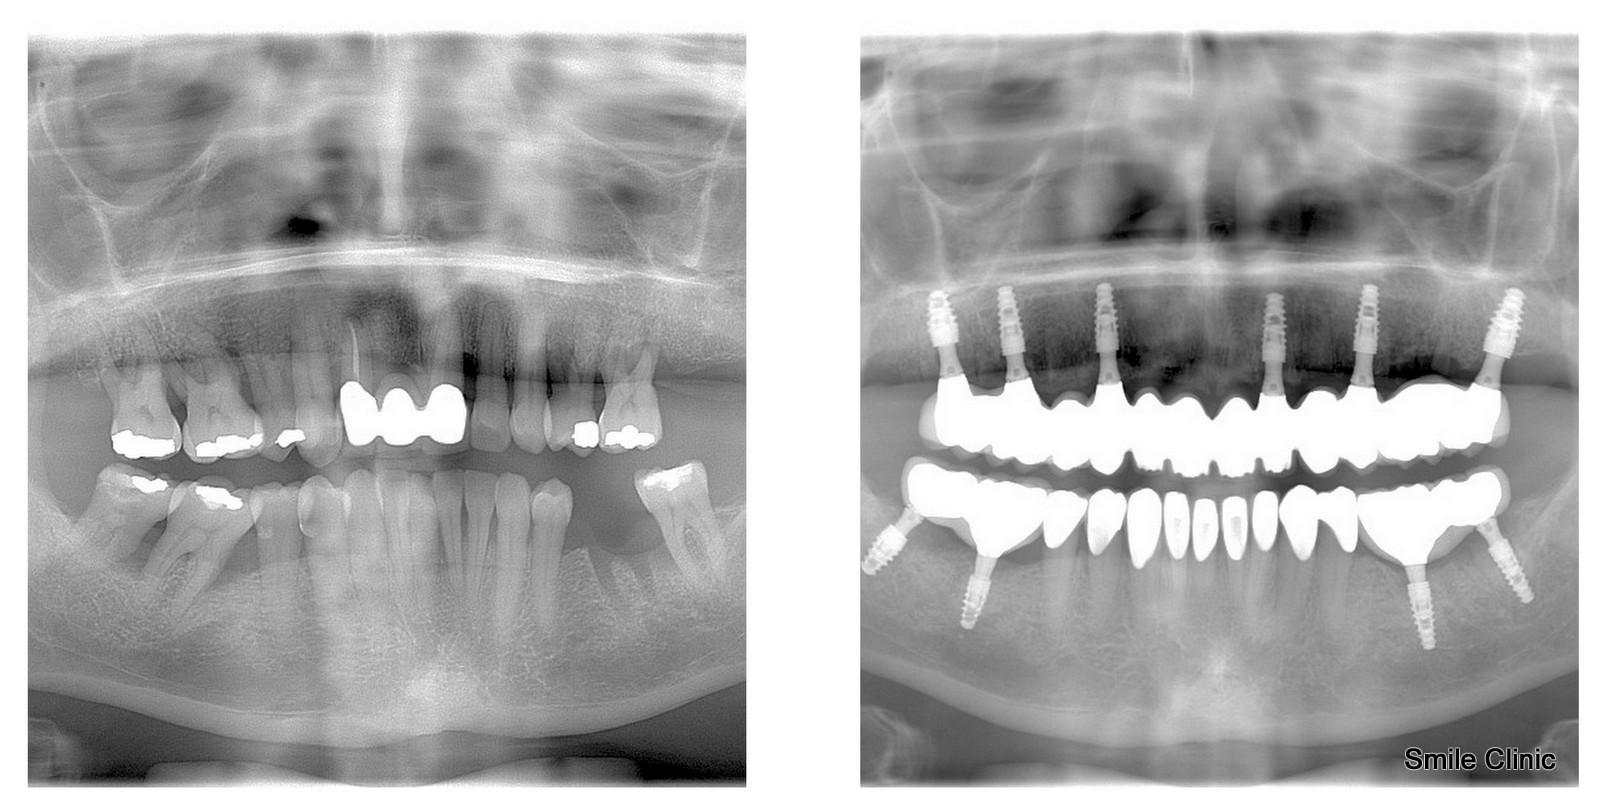

X-rays before the treatment and after the treatment

Mrs Pamela from Manchester, UK, contacted us 2 months after her 50th birthday, and her wish was to have all her teeth replaced with dental implants and dental crowns. She made a booking at our dental clinic for a consultation, during which we took X-rays and a CT scan. The doctor, Dr Marek, recommended the All-on-6 treatment for her upper jaw. He suggested leaving her lower front teeth as they were in good condition and placing only 2 implants on the lower left and 2 on the lower right. After the consultation, Pamela decided to return to the UK and took her time to make the decision.

We were happy when Pamela contacted us again and booked an implantation session with Dr. Marek in June. Our driver picked her up at the airport and drove her to our dental clinic in Piešťany. Before the doctor could fit the implants, he had to extract 13 of her natural teeth. After that, in 5 hours, she already had her dental implants fitted in her mouth. The doctor has performed socket preservation for all of her dental implants to ensure successful root formation in her jaw.